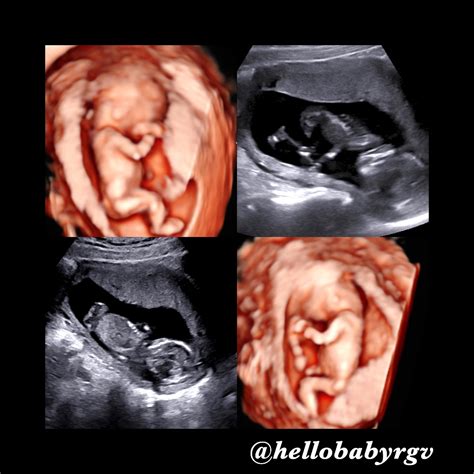

13 Week Gestation Ultrasound

• 4d ultrasound at 13 weeks